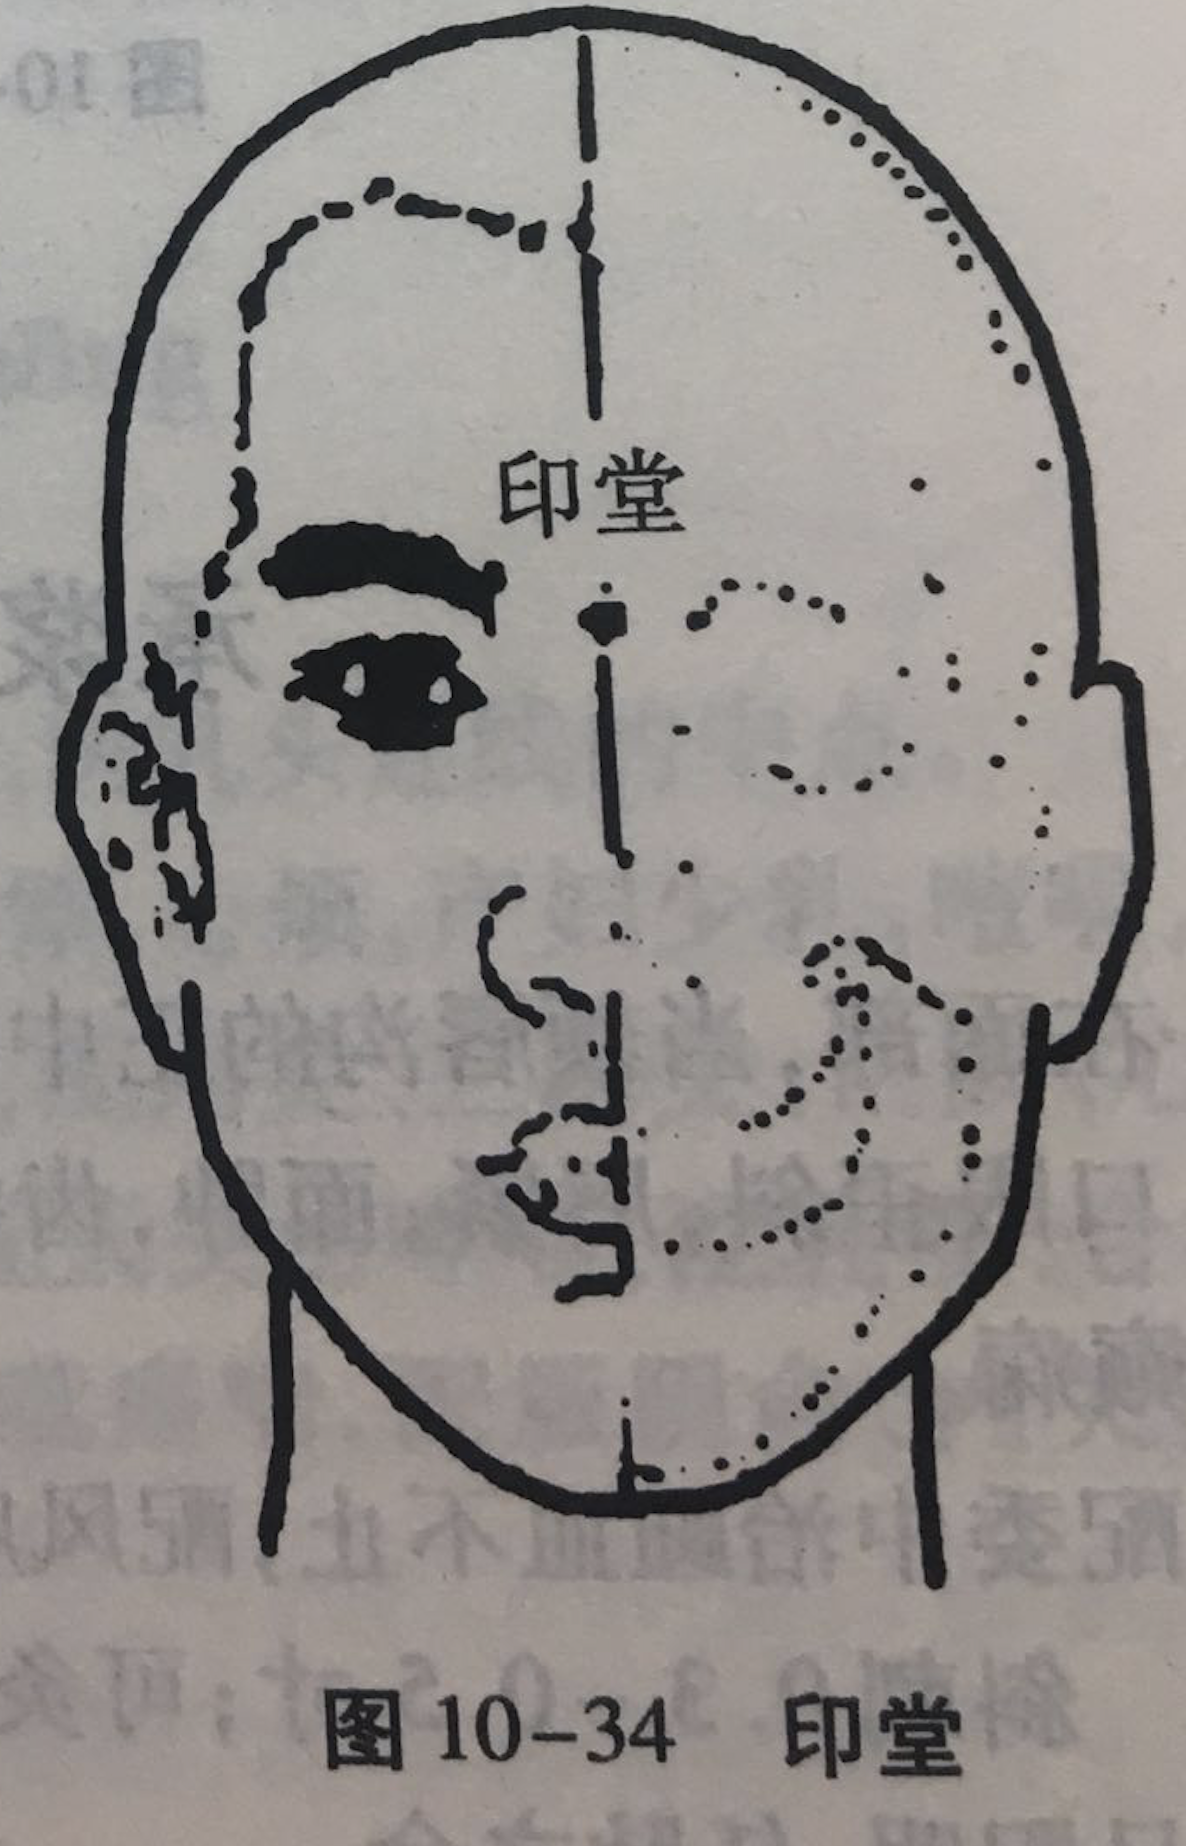

印堂

【定位】 在额部,当两眉毛内侧端连线中点(图 10-34)。

【主治】 头额痛,眩晕,鼻渊,小儿惊厥。

【刺灸法】 向下平刺 0.3 ~ 0.5 寸。